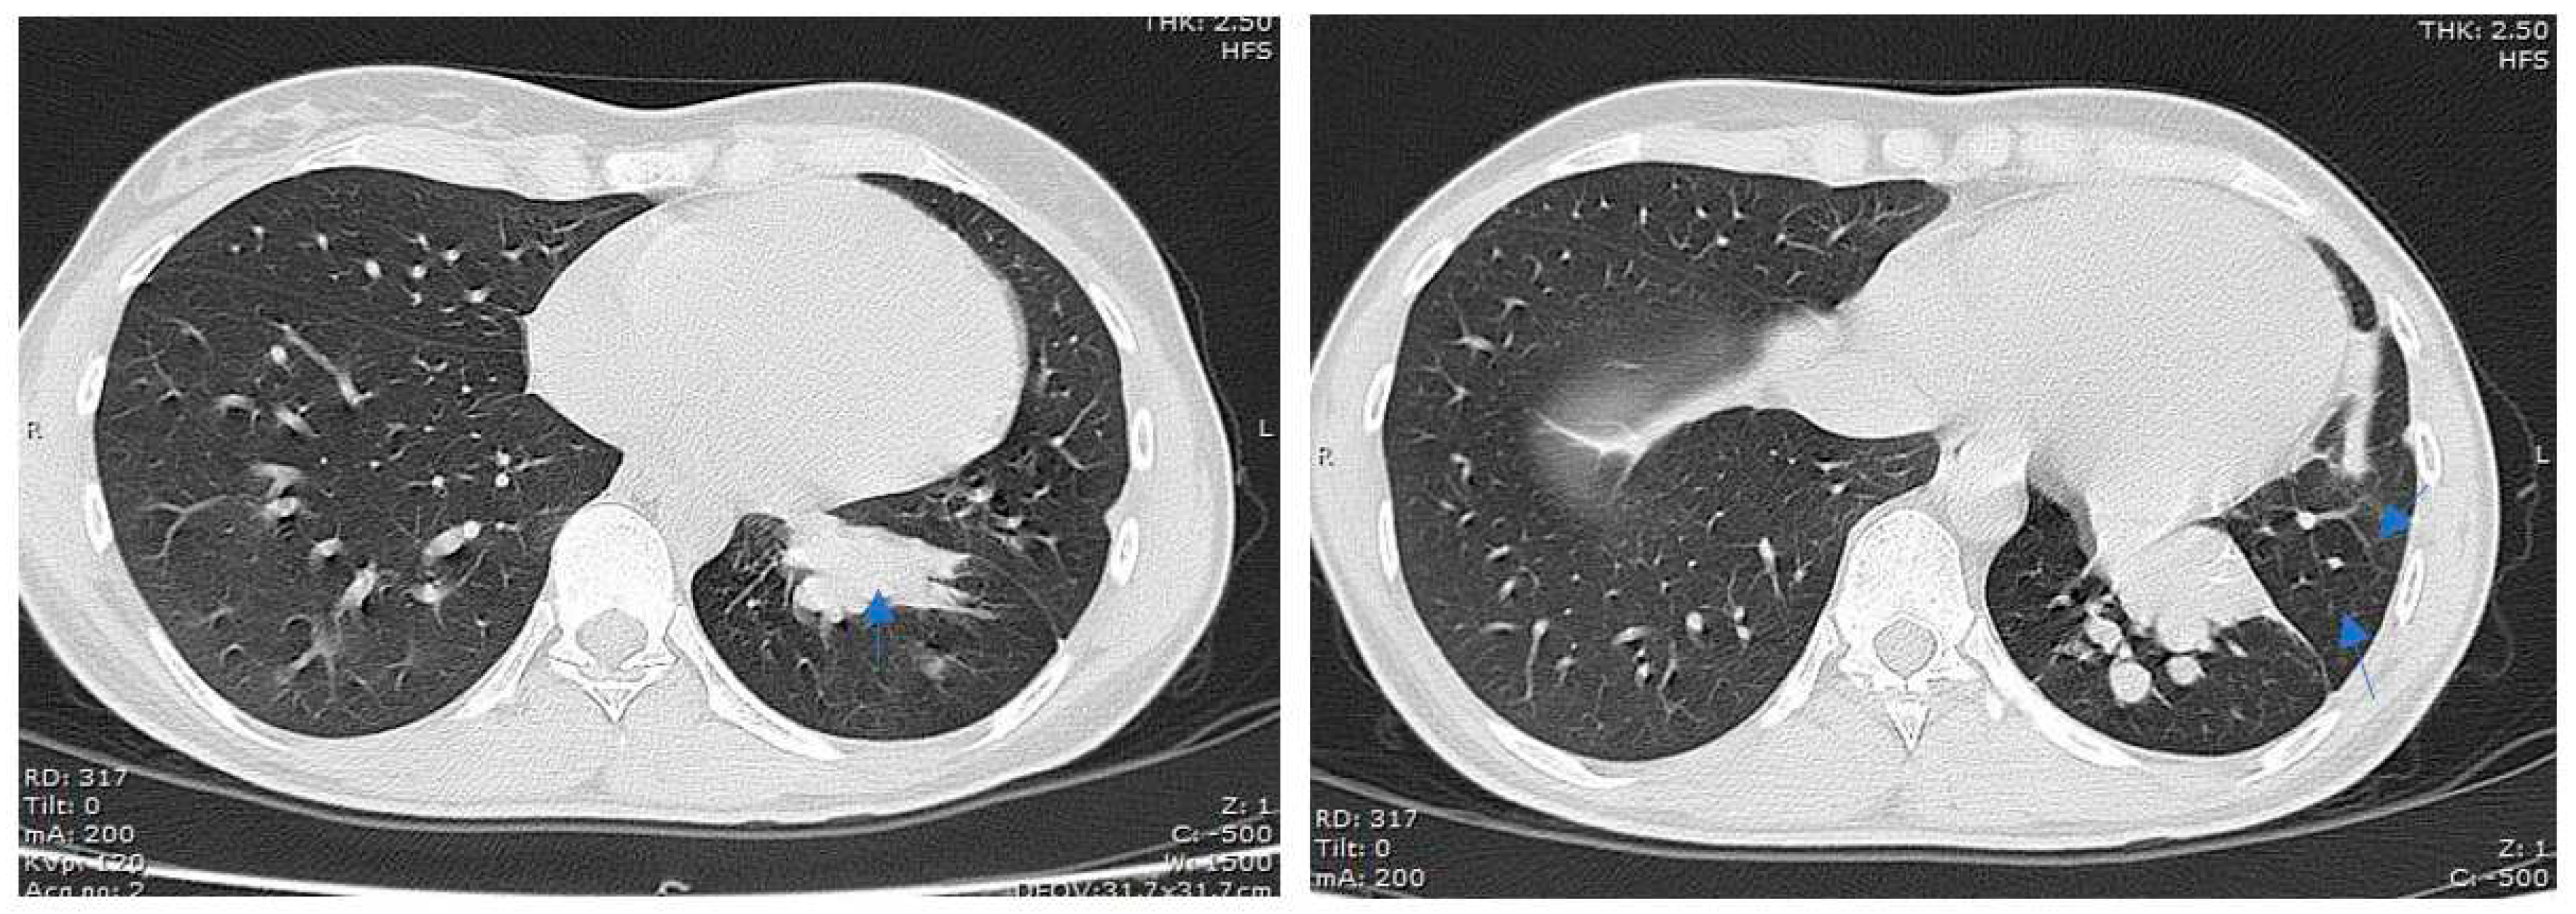

Case no 1.

Case no. 2